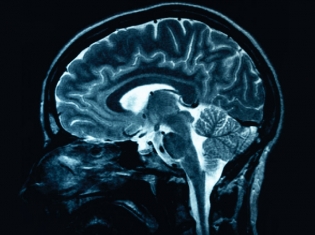

All of the 109 in the study progressed from mild cognitive impairment to AD during the five years. The researchers used magnetic resonance imaging (MRI) to look at their brains.

They looked at the way brain cells that were lost before and after the patient’s condition progressed to AD. An MRI was done when they were diagnosed with AD. MRI was also done one year before the diagnosis and one year after.